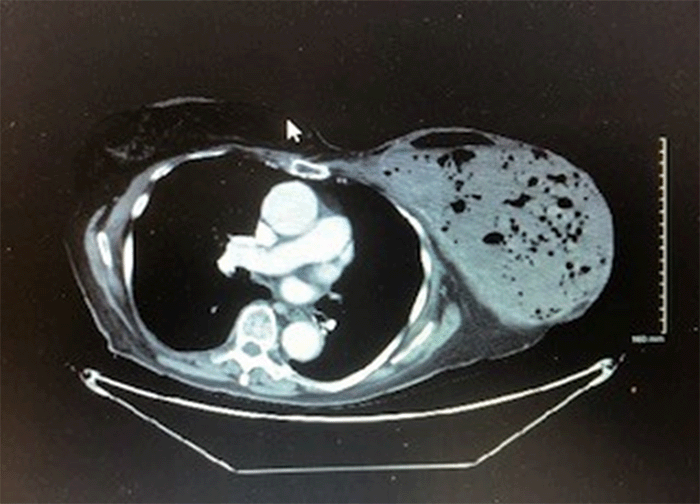

Chest CT identified a large, necrotic left chest mass measuring 14.1 cm × 19.0 cm × 20.3 cm with extension into the pectoralis major (Figures 2 and 3). Multiple enlarged left axillary lymph nodes were also identified, the largest measuring 3.0 × 3.5 cm (Figure 2, arrow). A pressure dressing was applied to achieve hemostasis.

Figure 2. Enhancing Partially Necrotic Left Chest Wall Mass with Adjacent Left Axillary Lymphadenopathy (arrow). Published with Permission

Figure 3. Enhancing Partially Necrotic Left Chest Wall Mass in Largest Dimension 14.1 cm × 19.0 cm × 20.3 cm. Published with Permission